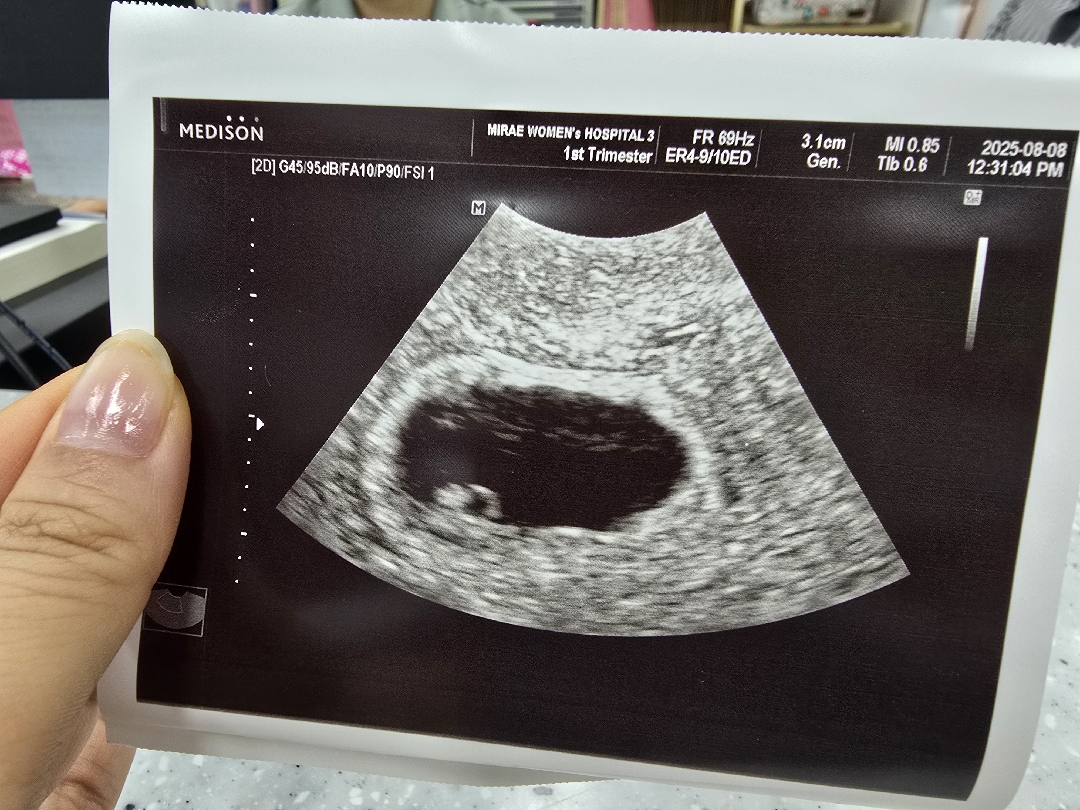

오늘 막생기준으론 6주5일인데 초음파상으론 5주5일이라네요 그래도 다이아반지도 보고 심장 뛰는거랑 아직 너무 작아서 크게 들리지는 않지만 작게나마 소리도 듣고 왔어요~ 산전검사때 자궁나이가 48세로 나와서 바로 난임병원가서 시험관하라고 들었는데 너무 고맙게도 허니문베이비로 와줬네요 다들 좋은 기운 받아서 건강하게 출산했으면 해요!!